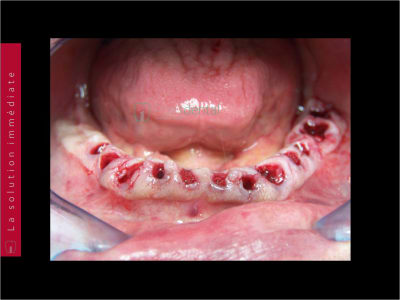

Bridge immédiat posé dans la continuité de la pose des implants

19/12/2022 à 07h25

Tu me demande les photos du cas et ton seul commentaire est de poster une photo de ton provisoire :)

Pour montrer qu'il est plus joli que le mien ? Et bien c'est vrai, je le trouve pas mal.

Cas bi-max réalisé selon le protocole de Dimitri, entierement délégué, pour une fois, a vivien, laboratoire LIO. Planif et guide réalisé avec Co-diagnostic, bridge prov PMMA rosenscrew réalisé en amont de la chirugie.